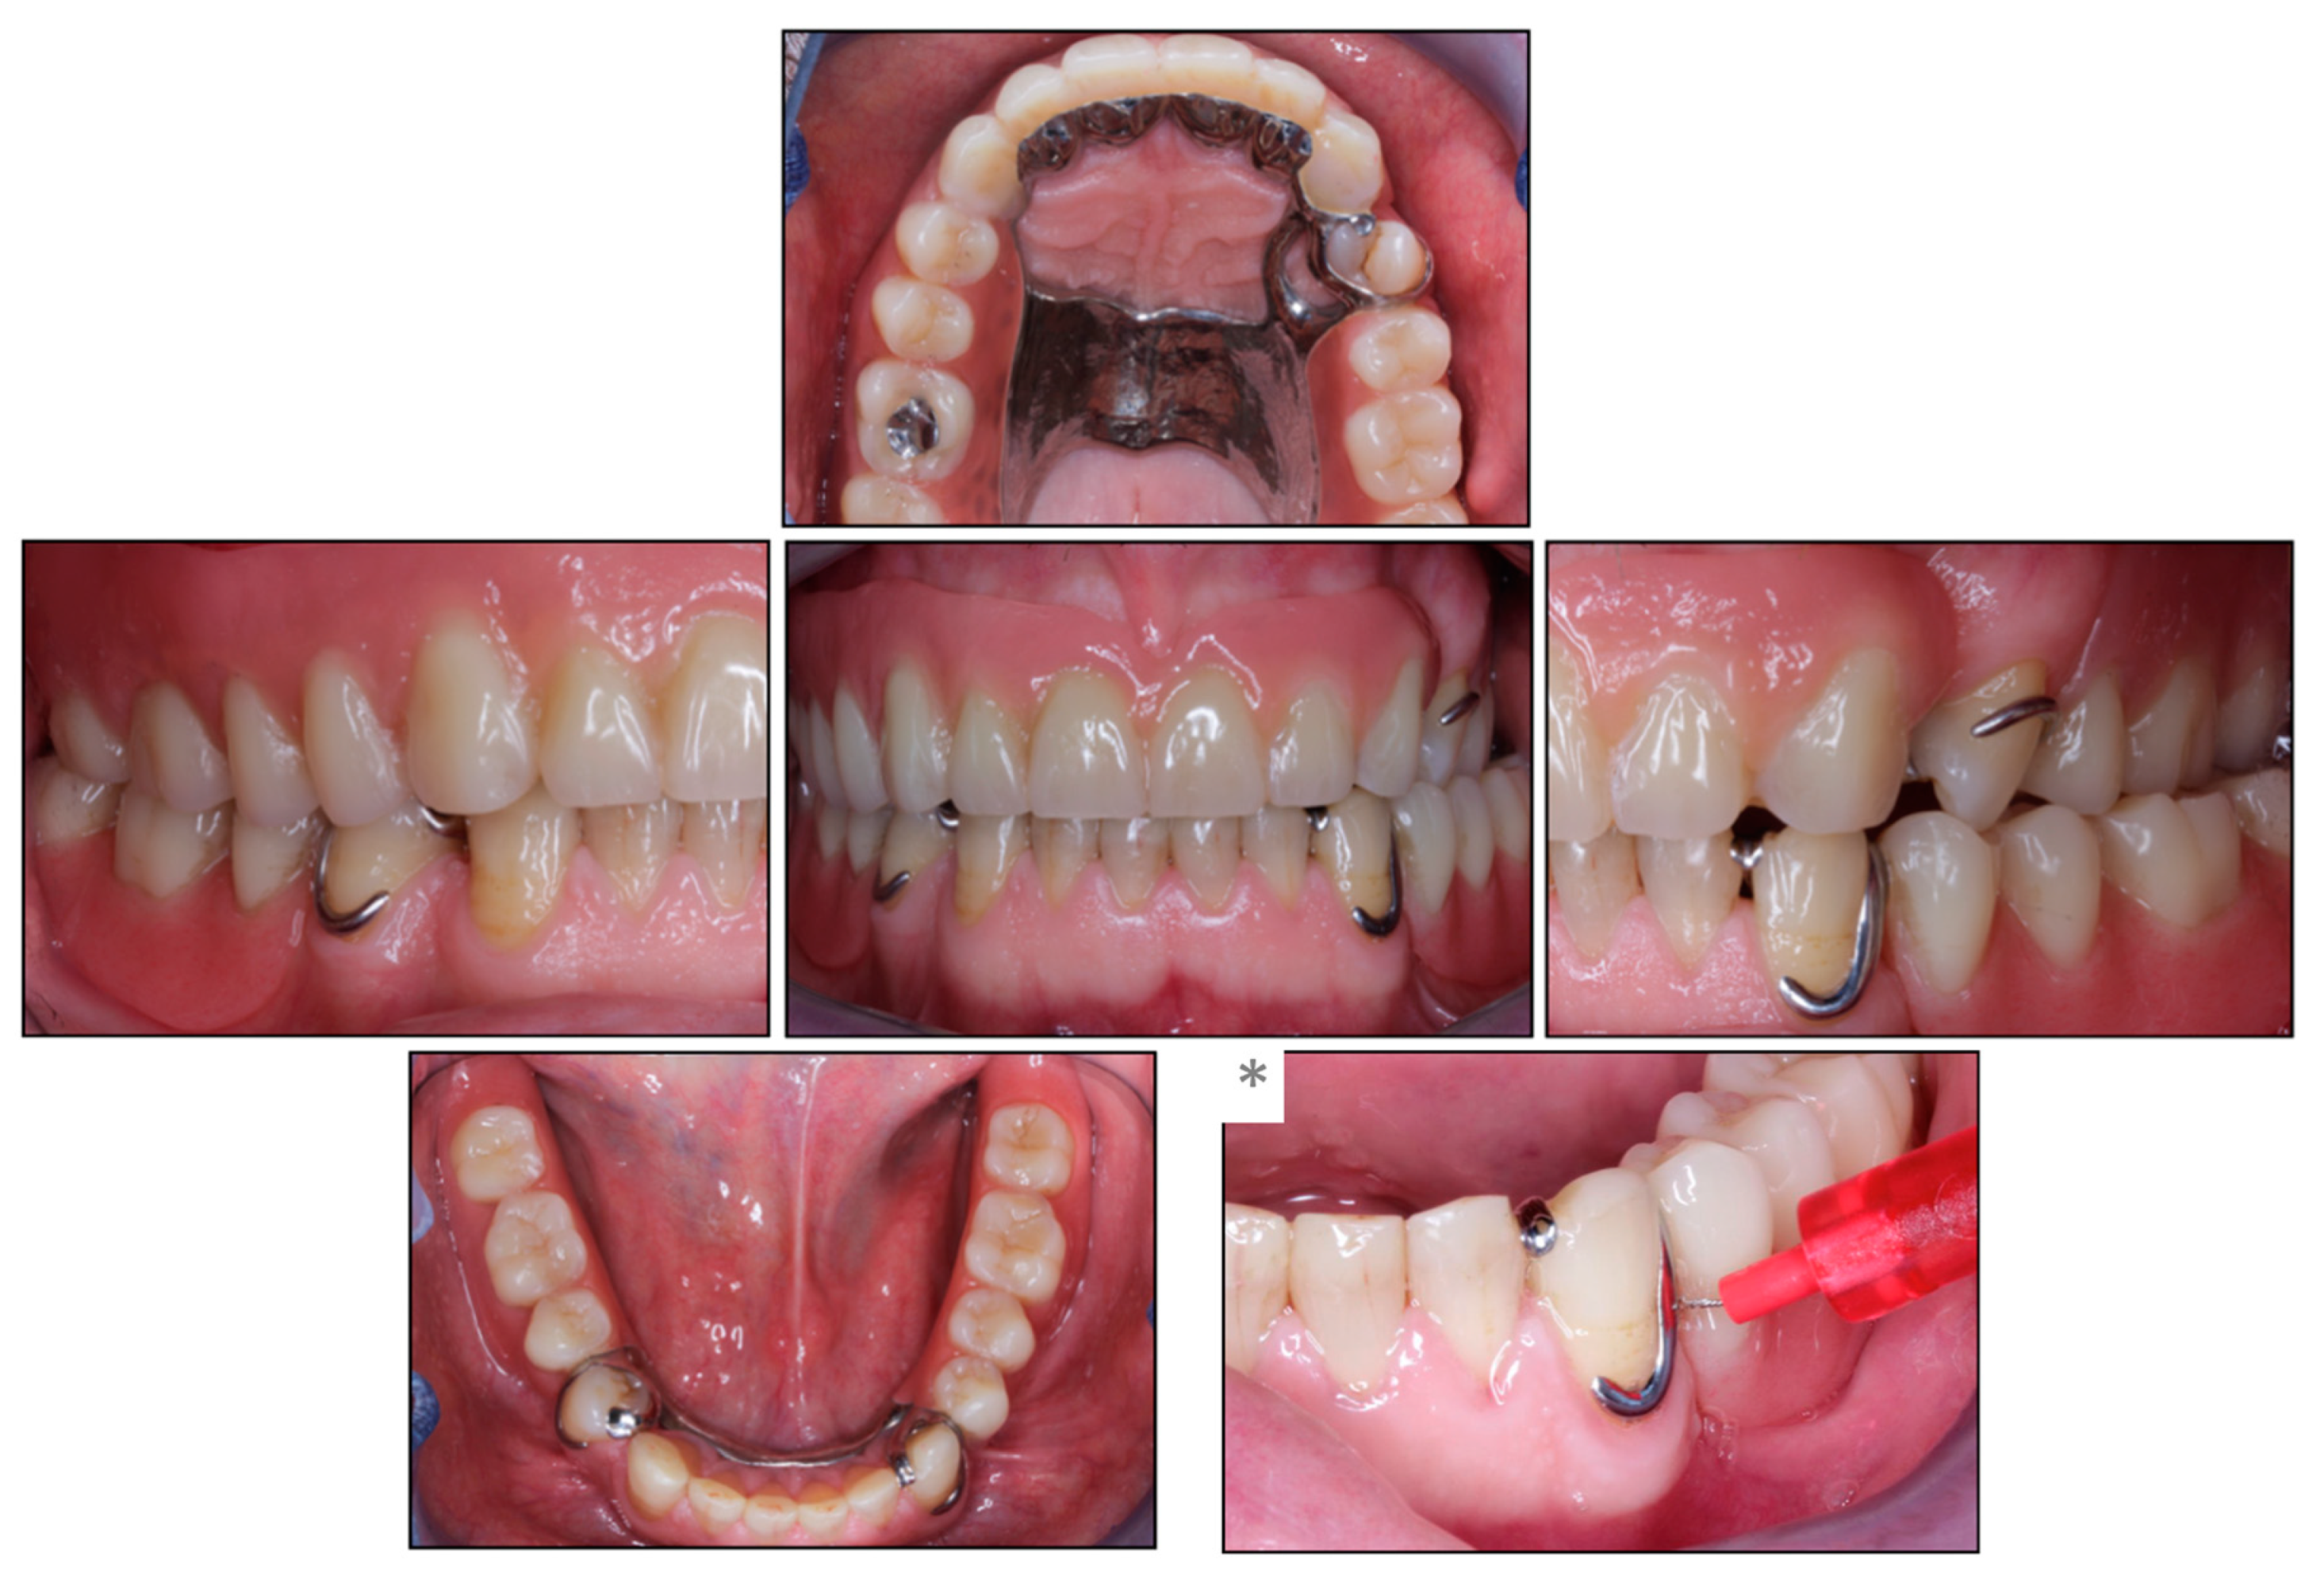

Due to the complex intermaxillary situation requiring an increase in the vertical dimension of occlusion (VDO), an overdenture prosthesis with anterior post copings and a clasp at the intact left premolar was planned in the maxilla, while a clasp-retained RPD was indicated in the mandible. The intact anterior dentition in the mandible determined the occlusal plane, and the increase in VDO was planned in the maxilla, which was restored first providing a diagnostic set-up in the mandible. For the RDP in the mandible, intraoral scans with and without the set-up were analyzed with a software program (3Shape Dental Manager, Copenhagen, Denmark), which enabled an exact planning of the prosthesis path of insertion and the position of the retentive clasp undercuts at the abutment teeth. This digital analysis replaced the traditional way with mounting casts in a surveyor to determine the path of insertion and undercuts at the abutment teeth (Figure 2a,b). Required occlusal rest cavities were prepared and a new intraoral scan was taken, which in turn was incorporated into the further planning. The RPD was then designed in the planning software and configured with 2 clasps at the most distal abutment teeth and an extension of the bilateral saddles to ensure support on the retromolar pads. In addition, the housings in the metal framework were scheduled for later implant healing abutments or retention elements in the area of the second molars (Figure 2c).

Following a 3-month submerged implant healing period, abutment connection was conducted, and retention elements were inserted (Novaloc, Straumann; Figure 4d–g). The height of the elements were selected taking into account the height of the mucosal peri-implant tissues and the vertical space (Figure 4d). Matrices were fixed in the RPD using self-curing methylmethacrylate resin (Unifast Trad, GC Europe AG, Luzern, Switzerland) (Figure 4f). The patient’s perception of the RPD before and after connection to the implant was assessed with questionnaires on function, stability, and satisfaction [18]; the OHIP-G14 and masticatory performance with a color mixing ability test [19]. Based on these, the patient indicated a beneficial impact on his perception and function after prosthetic rehabilitation with implant retention. Figure 5 shows the patient’s completed prosthetic restoration in both jaws (Figure 5) and Figure 6 provides an overview of the patient’s clinical treatment schedule (Figure 6).

Figure 2. (a,b) Planning tooth preparations for three clasp retentions, of which only the two most distal abutment teeth were restored with clasps, (c) final removable partial denture with housings for future implant retention or support (arrows).

Figure 5. Clinical situation after prosthetic rehabilitation. (*) Illustration of the cleaning ability in the proximal space distal to the abutment tooth with an interdental brush.